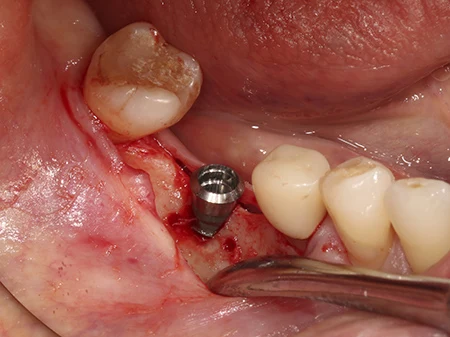

外側のインプラントのはみ出した部分に、人工の骨を移植していきます。